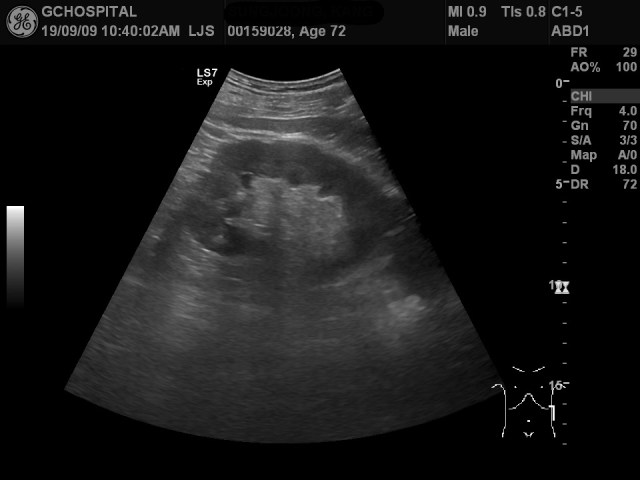

위의 두 영상은 같은 환자의 왼쪽 콩팥, 즉 좌측 신장을 촬영한 영상입니다. 위쪽 영상은 엎드린 상태에서 탐촉자를 등 뒤에서 접근해 얻은 영상이며, 아래 영상은 누운 상태에서 간초음파를 하는 도중 얻은 영상입니다. 환자분이 고령이고 깡마른 체형이었기 때문에 해당 부위가 움푹 파여있어서 좋은 영상을 얻기가 어려웠음에도 불구하고, depth, dynamic range 및 gain값을 제대로 맞춘 상태에서 정상에 가까운 신수질과 피질의 에코음영차이를 확인할 수 있었습니다.

이렇게 설정값을 적절히 조정하지 않고, 자세도 누운 상태 그대로 촬영했다면, 아래 영상처럼 신수질과 피질 사이의 에코음영차이를 보여주지 못해 왼쪽 콩팥의 신장질환이 오른쪽 못지 않게 진행해 있는 상황으로 잘못 파악할수 있었던 사례입니다.